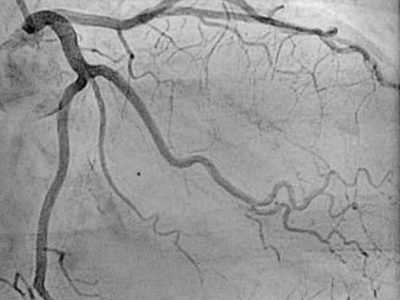

Coronary Angiography

Coronary Angiography is a procedure which is done to look for any blockages in the blood vessels of the heart